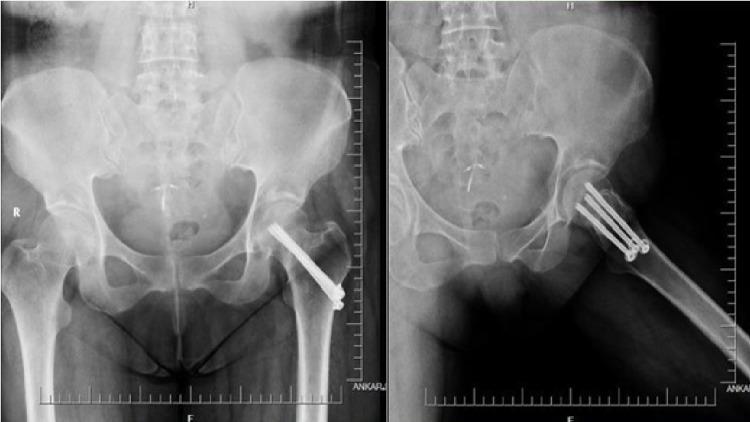

Twenty-six patients who underwent closed reduction and internal fixation by means of three cannulated screws due to femoral neck fracture between 2010 and 2014 were scanned retrospectively and included in the study. Harris hip scores of the patients at nine to 12 months were evaluated using the new index modified from Garden which is the sum of the differences from the ideal Garden index calculated on early postoperative anteroposterior and lateral pelvis radiographs.

The mean hip score was 73.1 (± 16.4), the minimum score was 32, the maximum score was 93. Postoperative anteroposterior radiographs revealed a mean Garden alignment index of 153.6°, the lowest value was 135° and the highest value was 168°. In the lateral radiographs, the mean Garden alignment index was 173.1°, the lowest value was 160° and the highest value was 178°. The mean value of the novel index was found as 14.2°, the lowest value was 2°, and the highest value was 40°. There was an inverse correlation between the novel index we defined and the Harris hip score (p<0.01).